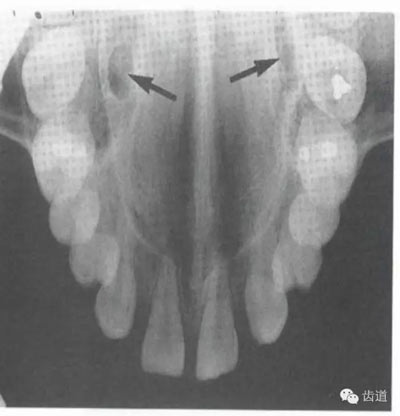

鼻腔位于上切牙根尖的上方,顯示為對(duì)稱性半圓形密度低的影像,其中間被一密度高的骨隔分開(kāi)為鼻中隔